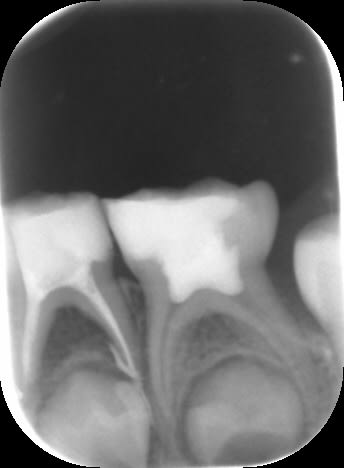

Ci-dessous, une pulpectomie avec un vilain dépassement mais ayant rempli son rôle : la 74 est restée sur l'arcade tout le temps nécessaire. Seconde radiographie 3 ans plus tard. Dommage pour l'apparition d'une carie distale sur 75 : la patiente n'était pas très sérieuse...

Img 1919 cyxq6q - Eugenol

1 jqhwda - Eugenol

2 sojyv3 - Eugenol